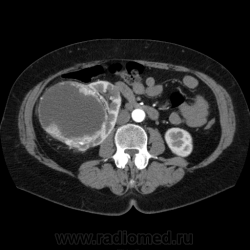

Солитарное кистовидное образование правой почки с неравномерно утолщенными стенками, у узлами в капсуле, накапливающими контраст. Фасция Гарота справа тяжистая. По классификации - киста 4-й категории, крайне велика возможность малигнезации. Может, показалось вовлечение парааортальных лимфоузлов?

В 1986 г. M.A. Bosniak создал “рабочую” классификацию кистовидных образований почек, которая позволяет предположить доброкачественность или злокачественность кистозных образований при распределении их по радиологическим критериям на 4 основные категории. Образования I и II категорий являются заведомо доброкачественными и поэтому нуждаются в динамическом наблюдении или, по показаниям, в лечебной пункции со склеротерапией под контролем УЗИ или КТ. Образования III категории могут быть как доброкачественными, так и злокачественными, а образования IV категории – кистозные почечноклеточные раки.

Третья категория – более сложные кистовидные образования, которые демонстрируют какие-либо радиологические признаки злокачественности. Некоторые из этих образований оказываются доброкачественными (например, сложные кисты, мультилокулярная кистозная нефрома, геморрагические кисты), другие злокачественными (почечные кистозно-клеточные карциномы). Одним из критериев, которые заставляютотнести кистовидное образование почки к III категории, является повышение плотности ее стенки. При КТ у кистовидного образования выявляется плотная (вплоть до обызвествления) стенка по всему периметру кисты, хотя образование может сохранять некоторые признаки простой кисты почки. Следующим критерием является характер отложения кальцинатов. Если при КТ в образовании определяется большое количество кальцинатов, расположенных глыбками (как на периферии образования, так и в центре), если из-за этого стенки и перегородки становятся утолщенными, неправильной формы, то данное образование следует отнести к III категории. Наличие множественных перегородок толщиной более 1 мм, видимых утолщений в месте прикрепления перегородок к стенкам кисты позволяет также отнести данное образование к третьей категории. Большое количество тонких перегородок в образовании определяет его как сложную кисту. Такие образования крайне сложно дифференцировать как доброкачественные или злокачественные, но они чаще по КТ-картине выглядят как злокачественные. При КТ определяется негомогенное многокамерное образование округлой или неправильной округлой формы, возможно с капсулой. Плотность образования неоднородная, пониженная относительно паренхимы, в полости образования видно большое количество перегородок.

IV категория – поражения явно злокачественные, обычно кистозные почечно-клеточные карциномы. Основными симптомами кистозной опухоли при КТ являются: неправильная форма кисты, негомогенность структуры образования с участками некроза, деформация почки, нечеткая граница между кистой и паренхимой почки, плотностные показатели могут быть выше, чем в кистах (+20…+40 Н), т.е. близкие к плотности почечной паренхимы. Капсула имеет неравномерную толщину, часто обызвествлена по периферии. Возможна визуализация дополнительных фокусов образования (кажущееся увеличение образования в размерах и изменение его конфигурации) после введения контрастного вещества. Но самым важным симптомом является увеличение плотности внутреннего содержимого после внутривенного введения контрастного вещества. Часто на серии срезов удается выявить эндофитные гребневидные фестончатые разрастания, выступающие в просвет кистозной полости. Особенно хорошо этот мягкотканый васкуляризированный компонент опухоли проявляется при внутривенном контрастировании

Всё верно, я тоже пользуюсь данной классификацией по Босняку, кистозно-солидное образование правой почки я отнёс к 4 категории, нужно отметить, что преобладает кистозный компонент, но солидный компонент довольно приличный и значительно накапливает контрастное вещество до 80-90HU, четко капсулу образования не отграничить. Ко всему этому в паренхиматозную фазу четко дифференцируются единичные парааортальные и паракавалльные л/узлы. С большей степенью вероятности в данном случае cr почки. Пациентка на следующей неделе будет госпитализирована для верификации.

Описание изменений, выявленных при микроскопическом исследовании: опухоль представлена крупными альвеолярными структурами из светлых, оптически пустых клеток с мелкими гиперхромными ядрами, опухоль частично инфильтрирует капсулу почки, полностью прорастает стенку почечной лоханки, образуя полиповидные структуры. Одиночные опухолевые эмболы в сосудах почки. Отдельно присланный узел представлен тканью почки с опухолевым узлом, строение которого соответствует выше описанной опухоли. В воротах почки патологических образований не найдено. Во всех исследованных лимфоузлах (6 шт.) метастазы опухоли с замещением всей ткани лимфоузлов.

Патоморфологическое заключение: массивный светлоклеточный почечно-клеточный рак почки с частичной инфильтрацией капсулы, прорастанием в ЧЛС, опухолевыми эмболами в сосудах, множественными метастазами в забрюшинные лимфоузлы (6 шт